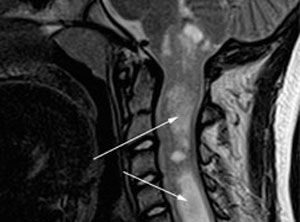

A primary clinical feature of NF2 is the development of schwannomas, tumors that grow along the nerve sheath. These tumors develop from Schwann cells, which support and protect nerve cells and serve as insulation needed to conduct information. Schwannomas that develop on cranial nerves (such as the eighth cranial nerve or the fifth cranial nerve) affect the head and neck. Tumors that develop on nerves that exit the spinal cord can cause weakness and numbness in the arms or legs. Peripheral schwannomas – tumors that develop in tiny nerves in the skin – usually don’t cause neurological problems but may present a cosmetic concern.